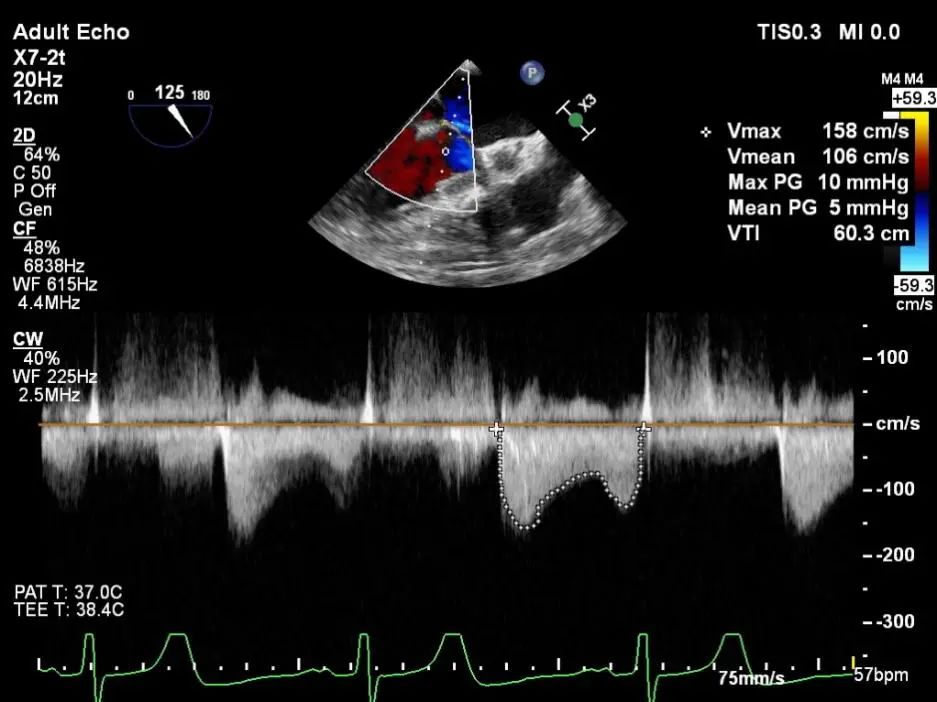

平均跨瓣压差:5mmHg

二尖瓣瓣口面积及平均跨瓣压差评估(5mmHg)